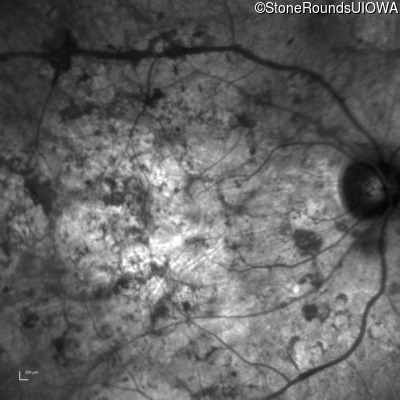

Infrared Fundus Photograph - Left - Hand Motion sc

Exemplar